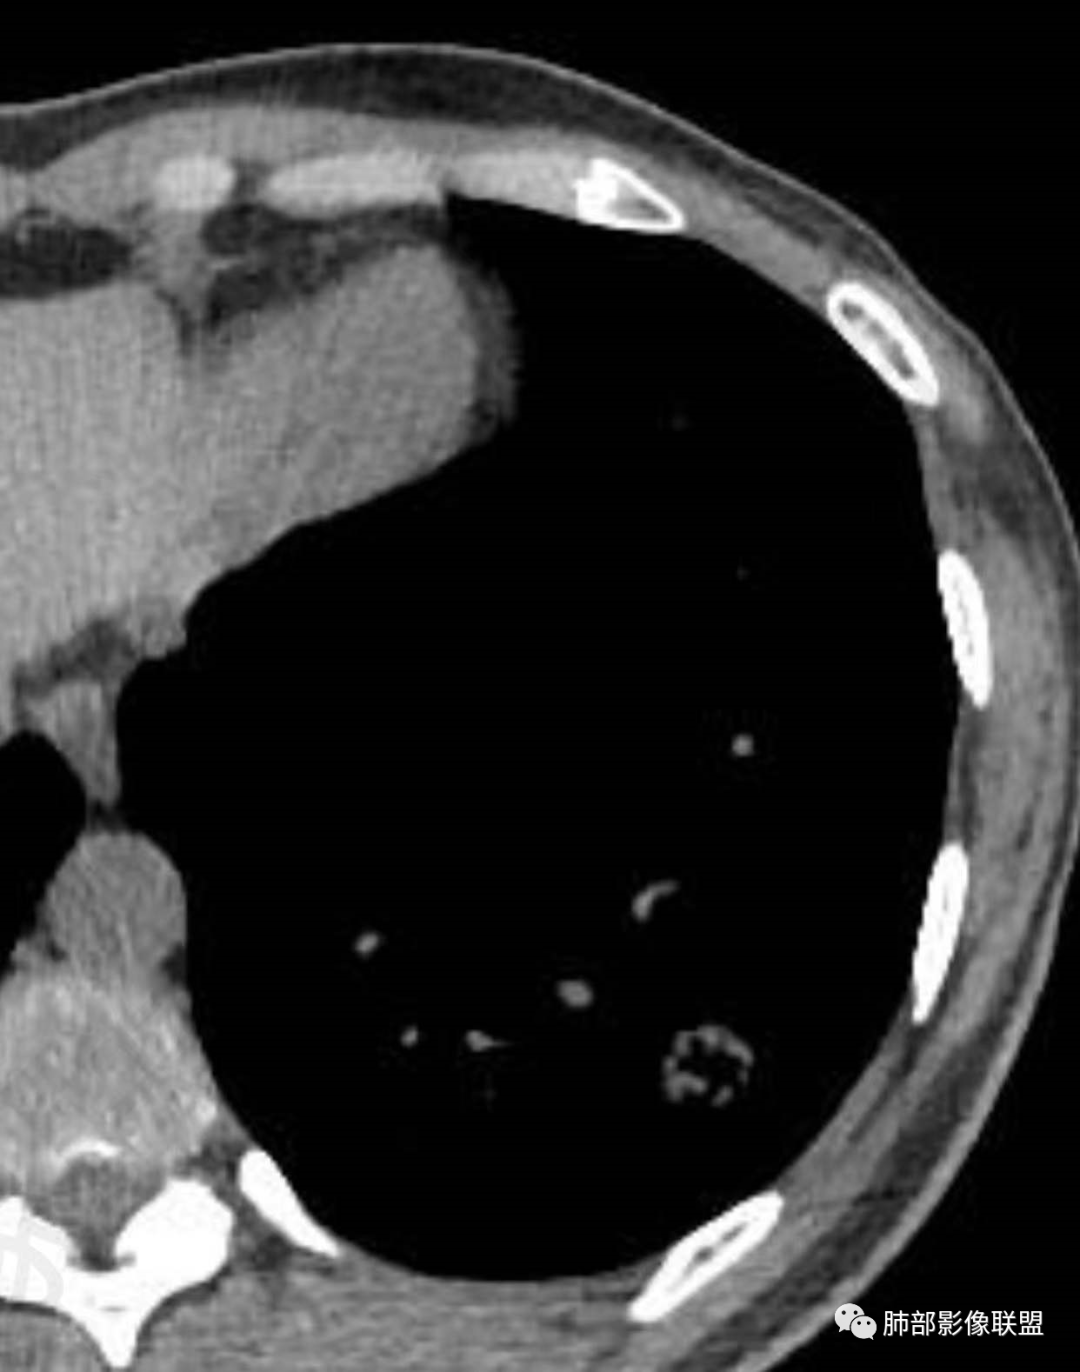

1、临床特点: 37岁女性,体检发现肺结节,2年前有甲状腺腺瘤手术史。实验室无阳性发现。

2、影像特点:左肺下叶类圆形结节影,周围可见多发细小毛刺,浅分叶,张力不高,未见胸膜牵拉。病灶内隐约见空泡影(未提供CT值),近端部分血管呈杵状增粗,可疑脐凹征。增强后实性部分有轻度强化。外围病灶,与支气管关系不明确。

4、病例小结:中青年女性偶然发现结节,表面欠光整,内部空泡,不均匀强化,边缘分叶毛刺等都具有影像学上的恶性征象,正如大多数老师所分析与肺腺癌较为符合。部分肺部肿瘤年轻化,尤其是肺腺癌等应当引发我们高度关注。